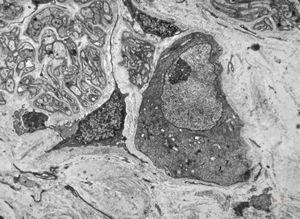

Whipple disease